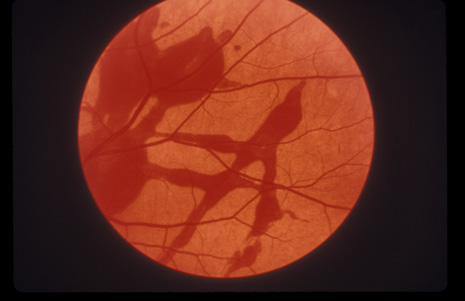

Retinitis sclopeteria is the rupture of the choroid or retina caused by shock waves generated by passage of a high-velocity missile through the orbit without directly striking the eye. Initially a subretinal or vitreous hemorrhage is seen. If the optic nerve is damaged, visual acuity can be profoundly decreased. In severe cases, massive amounts of fibrous tissue proliferate into the eye (Fig. 27). In others, as the blood clears, a claw-like break is often seen in Bruch's membrane and in the choriocapillaris (Fig. 28). Retinal detachment rarely occurs at the site of the injury, probably because of binding of the retina to the choroid by fibrous tissue, but late detachment from a break at a distal site can occur.97,98

Fig. 27. A: the left eye of a man who shot himself with a pistol. The bullet passed through both orbits, behind the globes. The optic nerve is at the left of the photograph. There is extensive fibrous proliferation. B: The right eye has considerably less retinal damage, but the visual acuity is hand movements because of optic atrophy.

Fig. 28. A: An equator plus photograph shows retinitis sclopeteria. B: Higher power view of the sclopeteria.